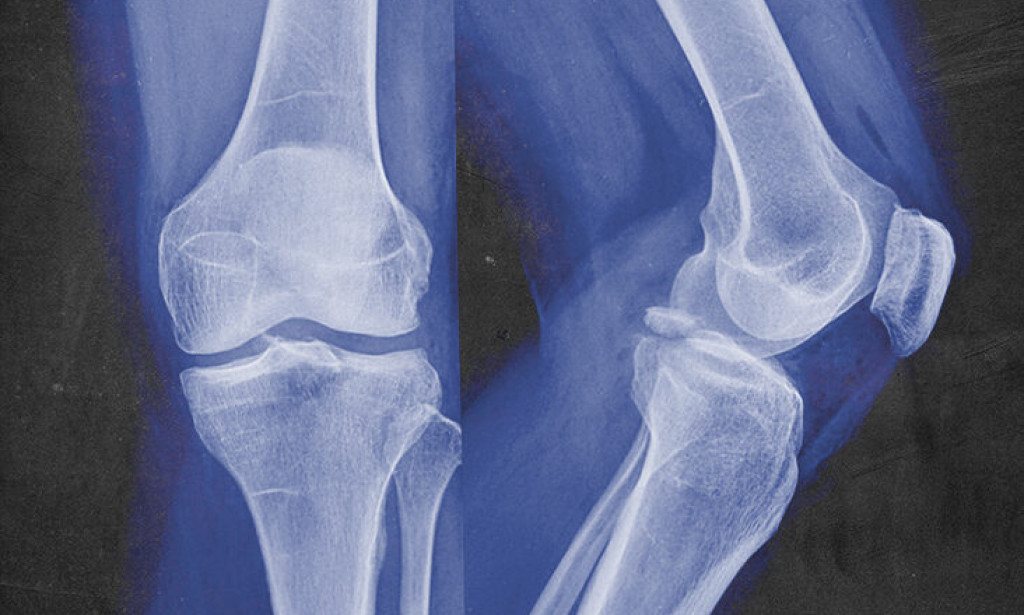

It's a lamentable result of living longer: bone misfortune. As time passes after the period of around 30, every one of us, and more quickly in ladies than men, experience diminishes in bone mineral thickness (the mineral substance of bone per unit of bone). Whenever bone mass falls beneath sound qualities, this is known as osteopenia, which can be an antecedent deep down illnesses osteomalacia or osteoporosis. Osteomalacia is impeded mineralization brought about by vitamin D and calcium insufficiency, while osteoporosis is extremely low bone mineral thickness that debilitates the skeleton, expanding defenselessness to bone breakage and cracks.